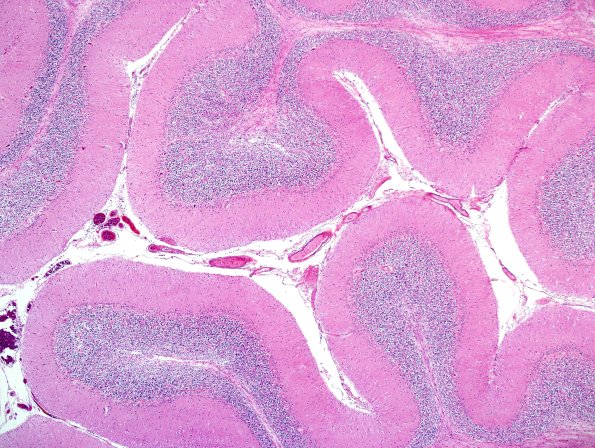

Washington University Experience | NEURODEGENERATION | Multiple Systems Atrophy (MSA) | 8D1 Multiple system atrophy (MSA, Case 8) Cbell H&E 3.jpg

8D1,2 There is severe neuronal loss in the Purkinje cell layer (and in the dentate nucleus, not shown). The deep white matter shows marked pallor, astrocytosis and scattered GCIs. (H&E) ---- There is severe neuronal loss in the Purkinje cell layer (and in the dentate nucleus, not shown). The deep white matter shows marked pallor, astrocytosis and scattered GCIs. (H&E) ---- Not shown: The substantia nigra shows severe neuronal loss and gliosis, accompanied by extracellular and phagocytosed pigment. GCIs are numerous throughout the midbrain, including the substantia nigra, red nucleus and are most frequent in the crus cerebri. No Lewy bodies are seen. There is no significant neuronal loss in the IML of the thoracic spinal cord and the residual neurons in the intermediolateral nucleus which do not show inclusions.. pSYN immunoreactive GCIs are present in relatively modest numbers in the central gray and white matter tracts. ---- Neuro Final Diagnosis: Multiple system atrophy (cerebellar variant; MSA-C, Gilman et al. PMID: 10223419). ---- Comment: Lewy bodies and Lewy neurites are not present anywhere in the neuroaxis so Parkinson's disease is excluded as a possible diagnosis. In the NIA-AA this is A1,B1,C0 and indicates only a low probability of cognitive impairment caused by AD. This patient's parkinsonism, autonomic dysfunction, and cerebellar signs are most likely explained by MSA .